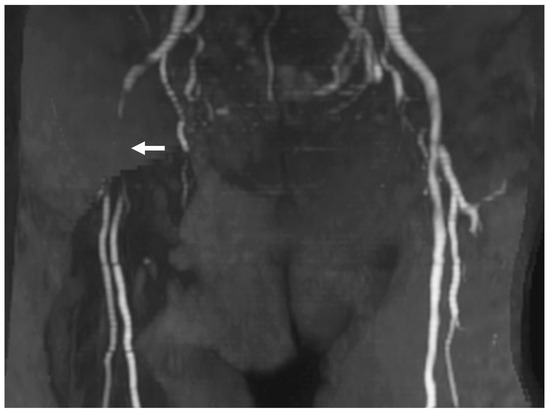

Figure 6. Femoral artery occlusion following TFA CAS. MRA demonstrates femoral artery occlusion after TFA CAS. In this case, a 9Fr BGC (outer diameter 3 mm) was introduced through a 9Fr sheath (outer diameter 3.7 mm) placed in the femoral artery (puncture size 3.7 mm). The occlusion caused symptoms of coldness, pain, and cyanosis (arrow: the femoral artery occlusion). Although conservative treatment led to some improvement, symptoms persisted. Abbreviations: CAS, carotid artery stenting; BGC, balloon guide catheter; MRA, magnetic resonance angiography; TFA, transfemoral access.